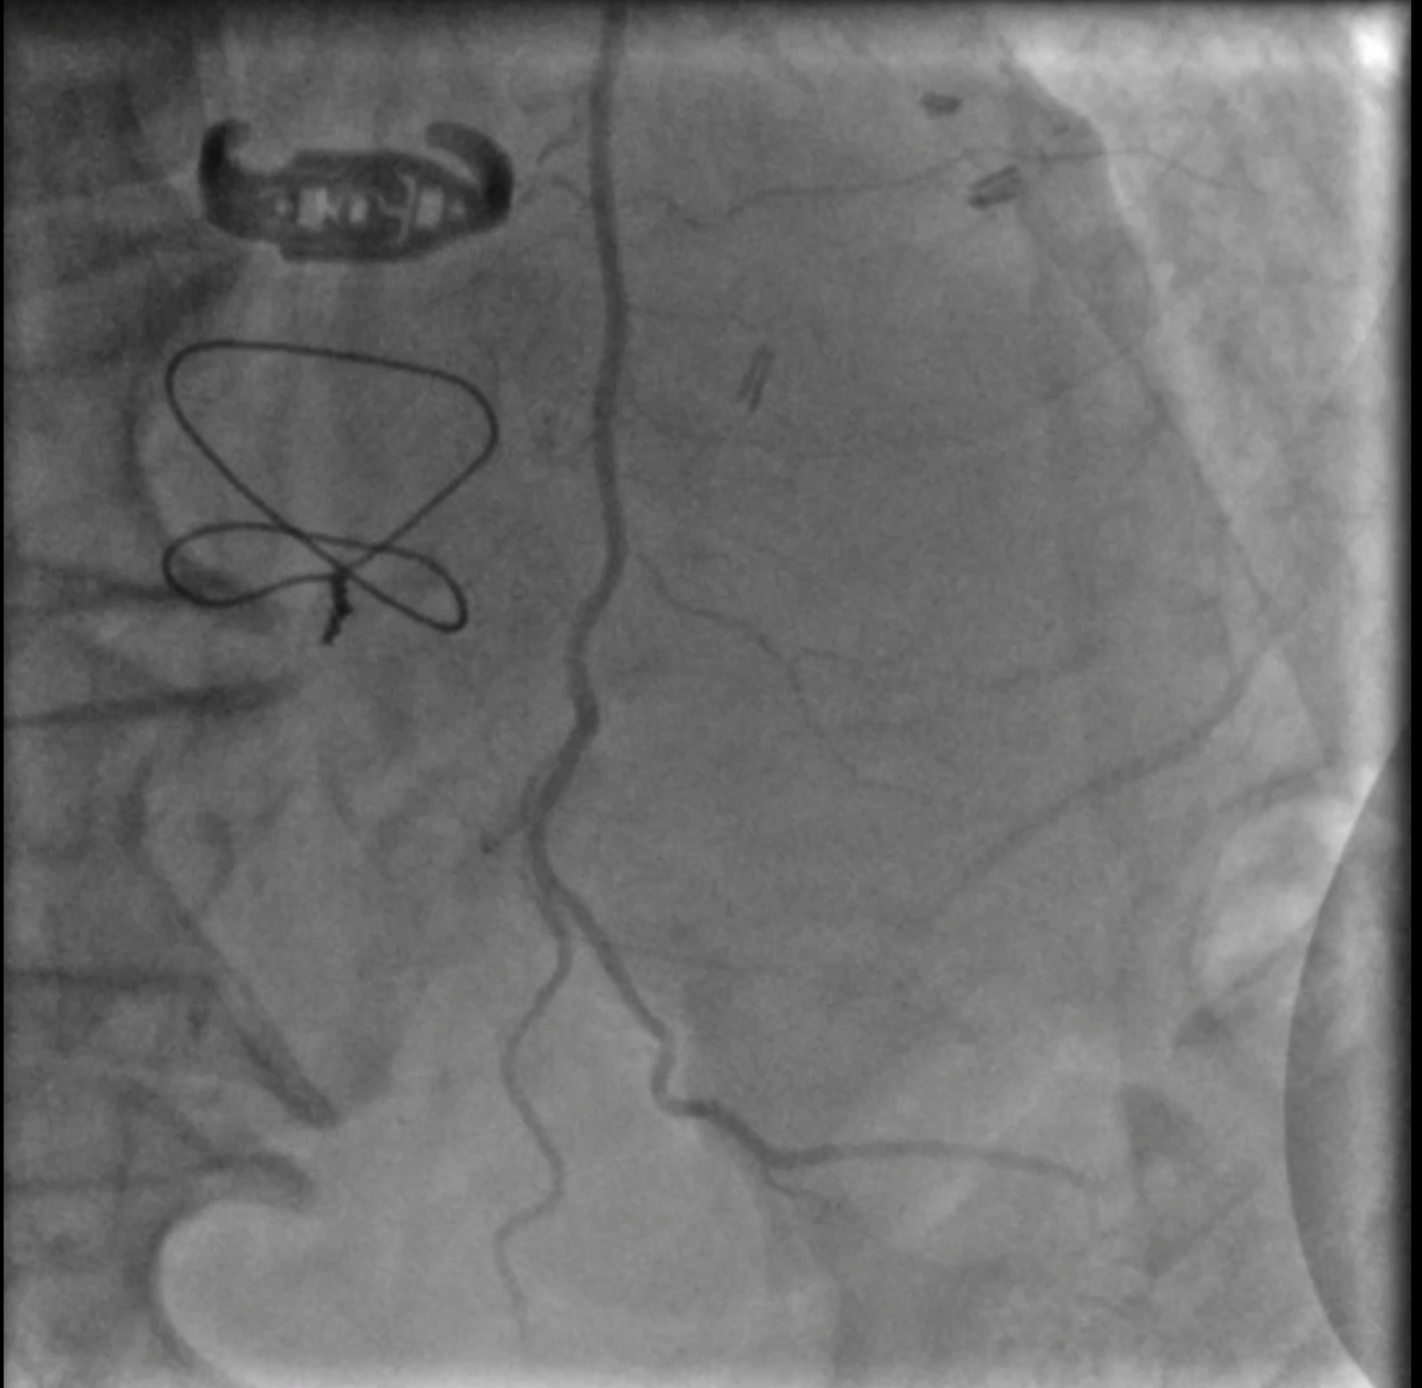

At the 1st encounter, RCA CTO PCI was performed with a plan for staged PCI of the left system. Using a 7F AL 0.75 for strong support, an antegrade approach with a double-lumen microcatheter and parallel wire technique (Pilot 150) successfully crossed the lesion. Predilatation with a 1.5 ¡¿ 15 mm balloon was done. IVUS could not pass due to 360¡Æ calcification. Rotablation with a 1.25 mm burr was attempted but limited to mid-RCA. Two DES were implanted from mid to proximal RCA, followed by post-dilatation.At the 2nd encounter, RCA stents were patent. PCI was done on LM, LAD, and D2. D2 was treated with DCB. LAD predilatation followed by OCT showed severe 330¡Æ calcification (max thickness 1.04 mm, MLA 1.63 mm©÷). IVL with a 2.75 ¡¿ 12 mm balloon (30 pulses) achieved multiple calcium fractures. A 2.75 ¡¿ 33 mm DES was deployed with good OCT results.At the 3rd encounter, 6 months later, the patient presented with ADHF. Angiography revealed RCA ISR CTO at the mid-bending site. The lesion was crossed with a Pilot 200 wire; predilatation showed a dog-bone sign. We do balloon based strategy for plaque modification using cutting, scoring, and double-wire balloons. IVUS showed stent underexpansion with 270¡Æ calcification and distal RCA stenosis. IVL with 2.5 and 2.75 mm balloons optimized the lesion, followed by two DES from distal to mid RCA. Post-PCI IVUS confirmed good result.